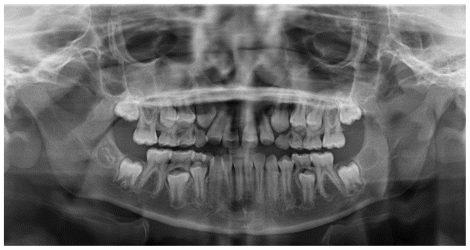

The patient was a growing female child who presented during early mixed dentition with an anterior crossbite associated with a deep overbite and a marked sagittal discrepancy (Figures 12–19). The initial clinical examination revealed a negative overjet, complete anterior deep bite, and a functional Class III occlusal pattern. Extraoral assessment showed a flattened facial profile, while cephalometric analysis confirmed a skeletal imbalance characterized by increased SNA and SNB values, an ANB of 0°, negative Withs appraisal, and significant dentoalveolar compensations, including proclination of both upper and lower incisors (Table 3). The vertical pattern was predominantly hypodivergent, suggesting a high risk of unfavorable mandibular growth progression if left untreated. Given the patient’s young age and growth potential, an early interceptive treatment was planned to use the AMCOP® TC appliance, with the aim of correcting the anterior crossbite, improving neuromuscular balance, and guiding sagittal and vertical development during growth. The appliance was worn nightly and for additional daytime hours, according to patient compliance.

After 18 months of treatment, a clear clinical improvement was observed. Intraoral examination demonstrated complete correction of the anterior crossbite, with establishment of a positive overjet and normalization of the anterior occlusal relationship. The deep bite was reduced, allowing more functional anterior guidance. Occlusal relationships improved toward a stable dental Class I, and the need for excessive dentoalveolar compensation was reduced. Cephalometric reassessment showed an overall improvement in sagittal relationships and incisor inclinations, with a trend toward normalization of the previously altered parameters. These findings indicate that early functional therapy with the AMCOP® TC appliance was effective in intercepting the developing Class III malocclusion, improving occlusal function, and potentially reducing the severity of future skeletal discrepancies (Table 4).